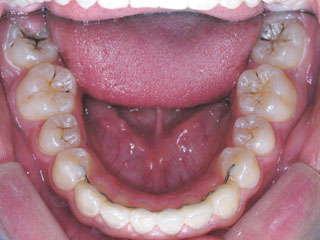

保定治療に移行してから3年半が経過しました。上の顎に生えてきた親不知は下の顎の奥歯と噛み合うようになりましたが、下の親不知は、斜めに埋まっていましたので、噛み合わせへの変化を防止するためにも早めに抜いて貰いました。矯正治療ではなるべく長期に渡って、管理を行いますが、2年3年と大きな変化が無く、緊密な噛み合わせが確保出来ていれば、将来的にも安定が期待出来ると思います。